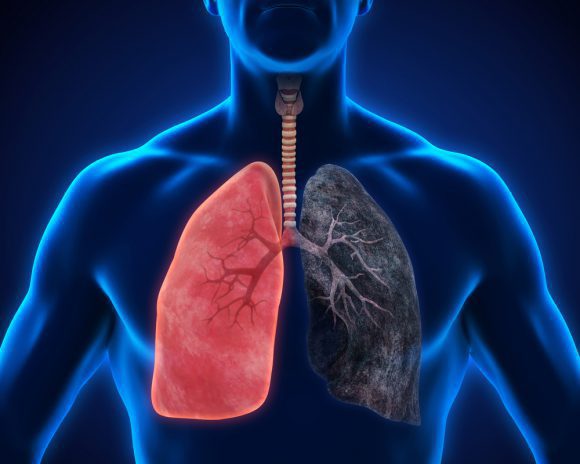

둘째, 환경적 요인이 '폐암'으로 이어질 수 있습니다. 일상 생활에서 흡입되는 발암 물질은 폐암을 유발할 수 있습니다. 즉, 대기오염 가스 중의 발암물질을 흡입하거나 흡연을 통한 발암물질을 직간접적으로 흡입함으로써 폐암이 발생할 수 있습니다. 흡연은 폐에 매우 치명적이어서 흡연은 폐암의 가장 큰 원인이며, 비흡연자도 간접흡연으로 폐암에 걸릴 수 있습니다.

흡연자가 주변에 있으면 비흡연자도 영향을 받는다는 연구 결과가 있습니다. 폐암은 다른 많은 환경적 요인으로 인해 다양한 원인이 있습니다. 또한 폐암은 주로 노인에게 영향을 미치며 40세 미만보다 70세 이상 인구가 더 많습니다. 따라서 나이가 들어감에 따라 정기적인 건강 검진이 필수적입니다.